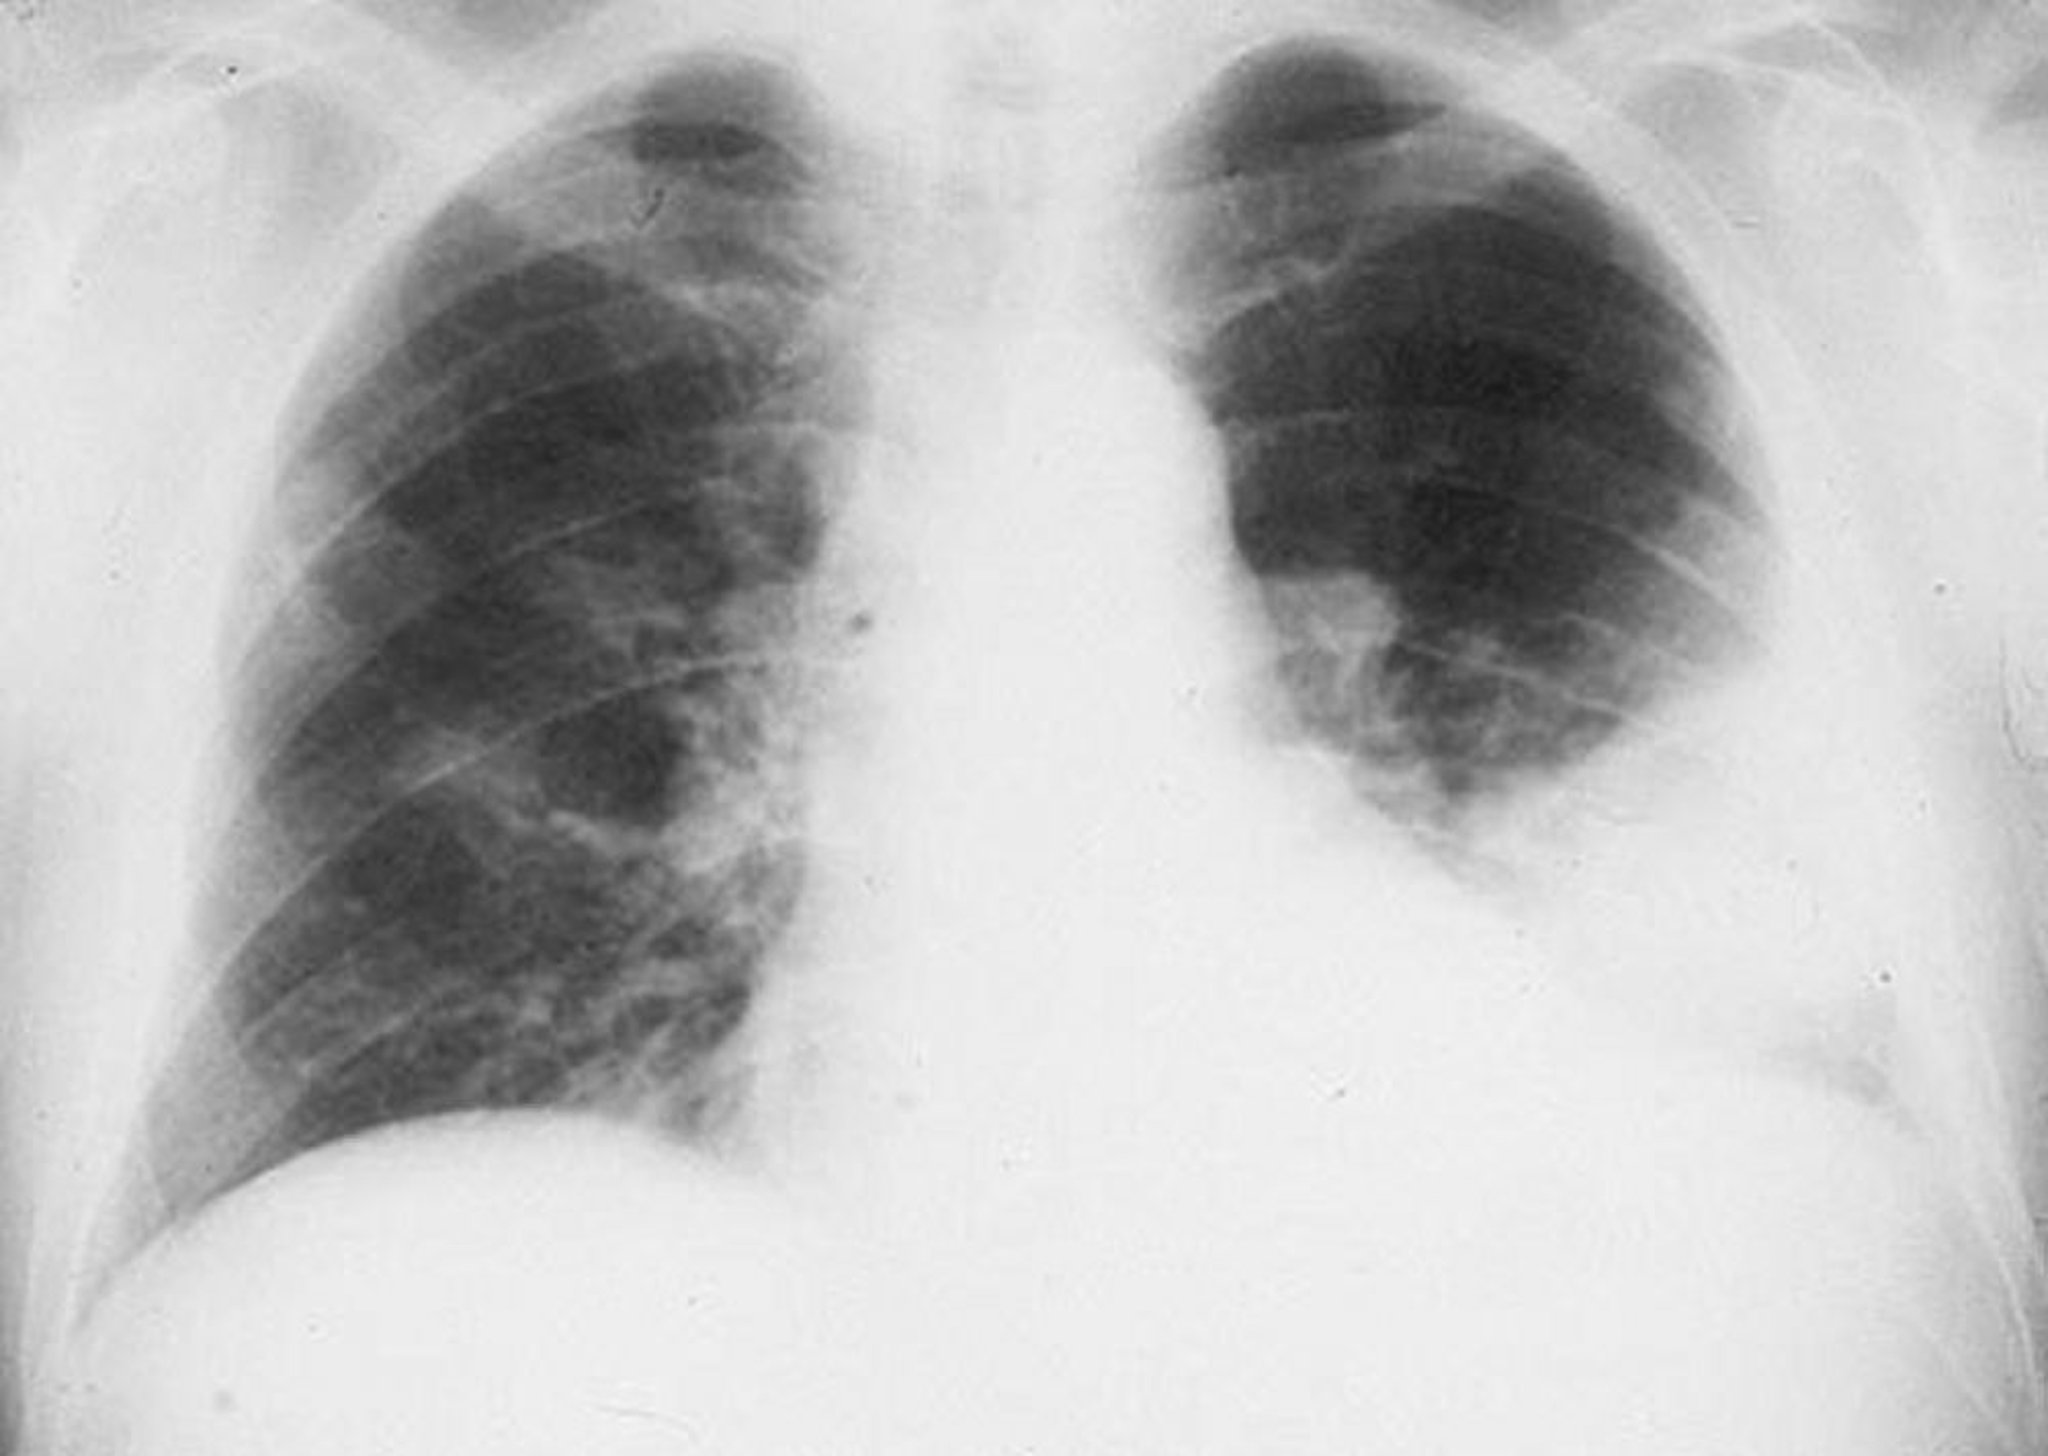

Infiltrado no lobo inferior esquerdo

Infiltrado alveolar no lobo inferior esquerdo em um homem com pneumonia bacteriana.

By permission of the publisher. De Roberts R. In Atlas of Infectious Diseases: Pleuropulmonary and Bronchial Infections. Editado por GL Mandell (editor de séries) e MS Simberkoff. Philadelphia, Current Medicine, 1996.